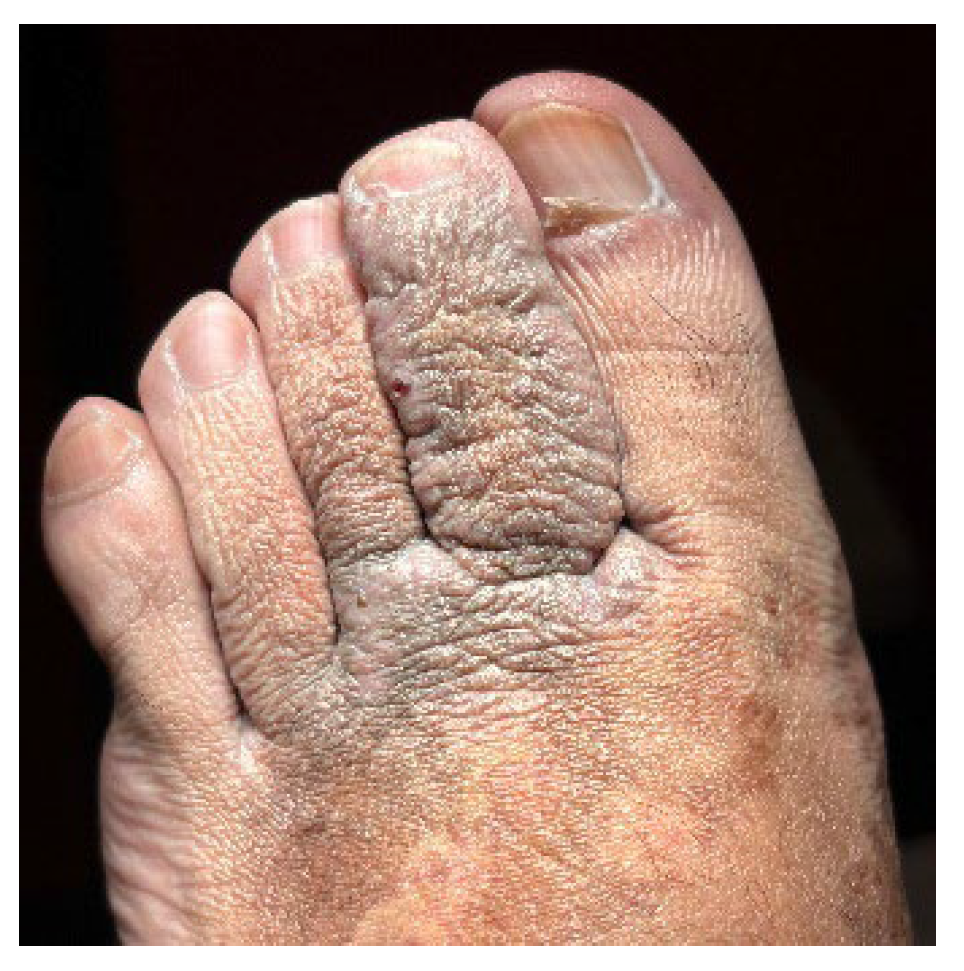

A 32-year-old healthy male presented with a brownish lesion on the dorsal surface of the left foot, evolving for 10 years. During this time the lesion progressively increased in size, involving the second, third, and fourth toes, and the medial border of the foot. Initially, the patient referred mild local pain, but in recent months developed mild pruritus. He denied systemic symptoms, mucosal involvement and similar lesions in other anatomical regions. He had no personal history of venous insufficiency, cardiovascular diseases or thromboembolic events. Physical examination revealed a brown plaque, with a focal erythematous hue, irregular borders, and ill-defined margins on the distal dorsum and medial border of the left foot. The lesion extended to the dorsal surface of the second, third, and fourth toes, here presenting with a thicker verrucous surface (Figure 1). Additionally, it extended towards the plantar surface of the distal and proximal/middle phalanges of the first and second toes, respectively (Figure 2). There were no palpable thrill or bruit and no oedema or varicous veins.

Figure 2. Lesion extension to the plantar surface of the distal and proximal/middle phalanges of the 1st and 2nd toes, respectively.